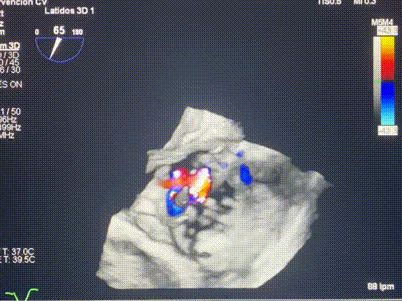

術(shù)后超聲顯示僅殘余微量瓣周漏